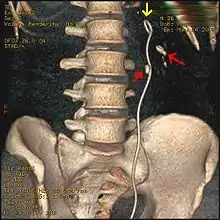

Three-dimensional reconstructed CT scan image of a ureteral stent in the left kidney (indicated by yellow arrow), with a kidney stone in the inferior renal pelvis (highest red arrow) and one in the ureter beside the stent (lower red arrow)

A kidney stone at the tip of an ultrasonic stone disintegration apparatus

Most stones under 5 mm (0.2 in) pass spontaneously.[29][7] Prompt surgery may, nonetheless, be required in persons with only one working kidney, bilateral obstructing stones, a urinary tract infection and thus, it is presumed, an infected kidney, or intractable pain.[100] Beginning in the mid-1980s, less invasive treatments such as extracorporeal shock wave lithotripsy, ureteroscopy, and percutaneous nephrolithotomy began to replace open surgery as the modalities of choice for the surgical management of urolithiasis.[7] More recently, flexible ureteroscopy has been adapted to facilitate retrograde nephrostomy creation for percutaneous nephrolithotomy. This approach is still under investigation, though early results are favorable.[101] Percutaneous nephrolithotomy or, rarely, anatrophic nephrolithotomy, is the treatment of choice for large or complicated stones (such as calyceal staghorn calculi) or stones that cannot be extracted using less invasive procedures.[47][7]

Ureteroscopic surgery

Ureteroscopy has become increasingly popular as flexible and rigid fiberoptic ureteroscopes have become smaller. One ureteroscopic technique involves the placement of a ureteral stent (a small tube extending from the bladder, up the ureter and into the kidney) to provide immediate relief of an obstructed kidney. Stent placement can be useful for saving a kidney at risk for postrenal acute kidney failure due to the increased hydrostatic pressure, swelling and infection (pyelonephritis and pyonephrosis) caused by an obstructing stone. Ureteral stents vary in length from 24 to 30 cm (9.4 to 11.8 in) and most have a shape commonly referred to as a "double-J" or "double pigtail", because of the curl at both ends. They are designed to allow urine to flow past an obstruction in the ureter. They may be retained in the ureter for days to weeks as infections resolve and as stones are dissolved or fragmented by ESWL or by some other treatment. The stents dilate the ureters, which can facilitate instrumentation, and they also provide a clear landmark to aid in the visualization of the ureters and any associated stones on radiographic examinations. The presence of indwelling ureteral stents may cause minimal to moderate discomfort, frequency or urgency incontinence, and infection, which in general resolves on removal. Most ureteral stents can be removed cystoscopically during an office visit under topical anesthesia after resolution of urolithiasis.[102]